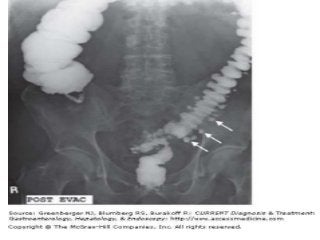

• Single-contrast barium

enema study

demonstrates

diverticulitis of the

descending colon with

fistula formation in the

small bowel.

demonstrates sigmoid

diverticulitis with a

colovesical fistula. Note

the contrast material in

the bladder.

diverticulitis with fistula

formation in the vagina.